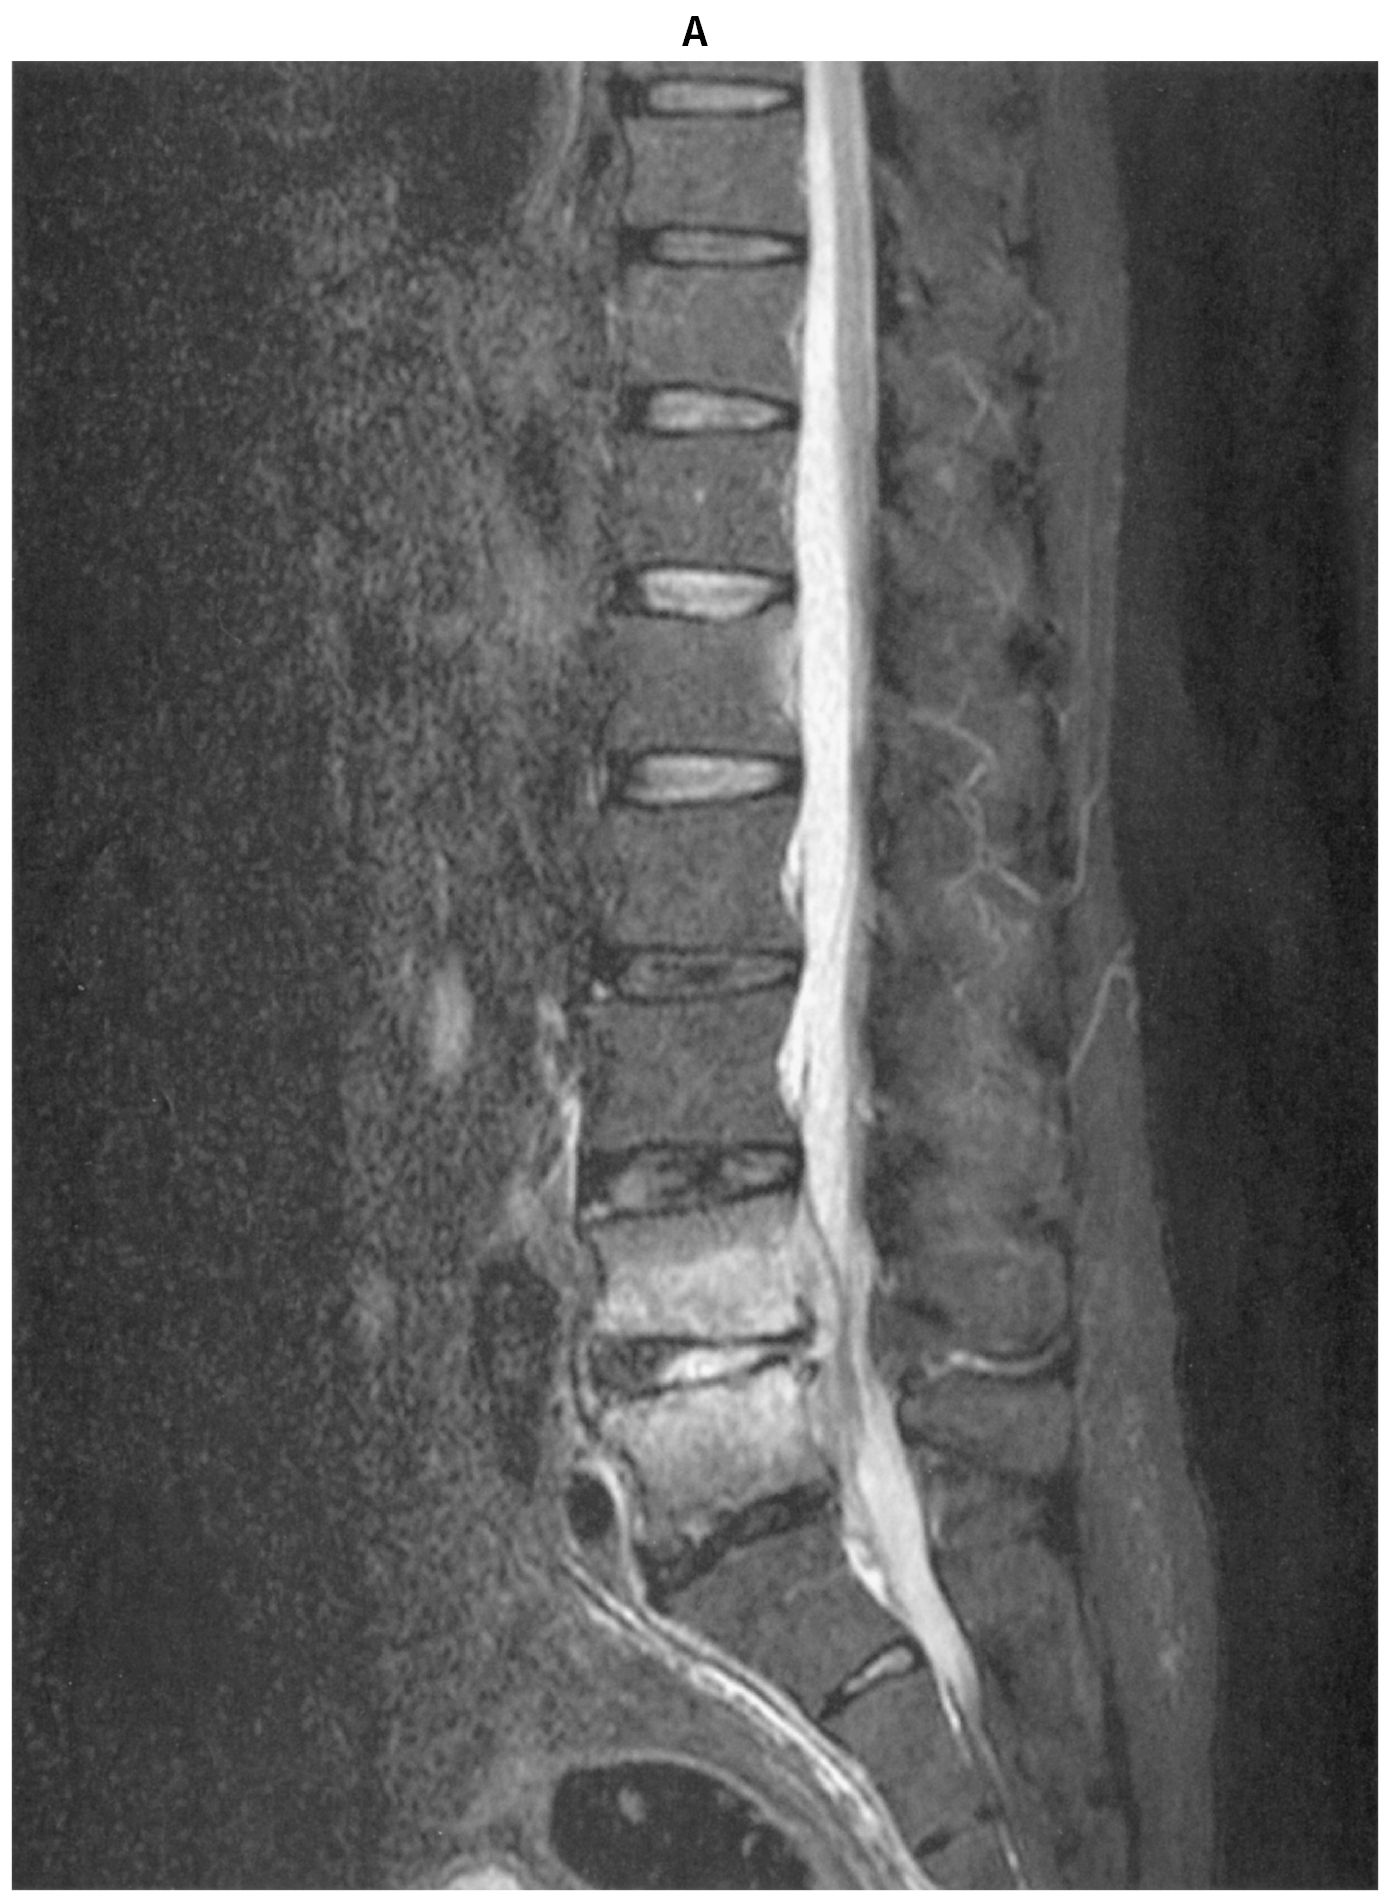

検査所見:血液所見:赤血球340万,Hb 12.4g/dL,Ht 37%,白血球11,100(好中球88%,好酸球1%,好塩基球1%,単球3%,リンパ球7%),血小板23万。血液生化学所見:総蛋白5.9g/dL,アルブミン2.6g/dL,総ビリルビン0.4mg/dL,AST 15U/L,ALT 11U/L,ALP 82U/L(基準38~113),γ-GT 11U/L(基準13~64),CK 50U/L(基準59~248),尿素窒素40mg/dL,クレアチニン3.7mg/dL,尿酸2.2mg/dL,血糖110mg/dL,HbA1c 5.8%(基準4.9~6.0),Na 143 mEq/L,K 3.5mEq/L,Cl 102mEq/L。CRP 14mg/dL。胸部エックス線写真で心胸郭比51%,両側肺野に浸潤影を認めない。腰椎単純MRIの脂肪抑制T2強調矢状断像(A)を下に示す。受診時に採取した血液培養が陽性となった。血液培養ボトル内容のGram染色標本(B)を下に示す。